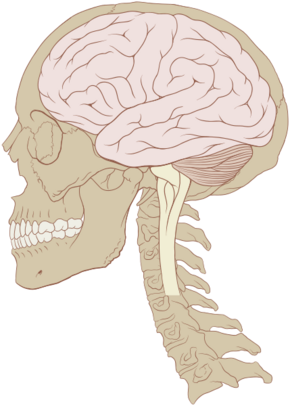

The human brain is the central organ of the human nervous system, and with the spinal cord makes up the central nervous system. The brain consists of the cerebrum, the brainstem and the cerebellum. It controls most of the activities of the body, processing, integrating, and coordinating the information it receives from the sense organs, and making decisions as to the instructions sent to the rest of the body. The brain is contained in, and protected by, the skull bones of the head.

The cerebrum, the largest part of the human brain, consists of two cerebral hemispheres. Each hemisphere has an inner core composed of white matter, and an outer surface – the cerebral cortex – composed of grey matter. The cortex has an outer layer, the neocortex, and an inner allocortex. The neocortex is made up of six neuronal layers, while the allocortex has three or four. Each hemisphere is conventionally divided into four lobes – the frontal, temporal, parietal, and occipital lobes. The frontal lobe is associated with executive functions including self-control, planning, reasoning, and abstract thought, while the occipital lobe is dedicated to vision. Within each lobe, cortical areas are associated with specific functions, such as the sensory, motor and association regions. Although the left and right hemispheres are broadly similar in shape and function, some functions are associated with one side, such as language in the left and visual-spatial ability in the right. The hemispheres are connected by commissural nerve tracts, the largest being the corpus callosum.

The cerebrum is connected by the brainstem to the spinal cord. The brainstem consists of the midbrain, the pons, and the medulla oblongata. The cerebellum is connected to the brainstem by three pairs of nerve tracts called cerebellar peduncles. Within the cerebrum is the ventricular system, consisting of four interconnected ventricles in which cerebrospinal fluid is produced and circulated. Underneath the cerebral cortex are several important structures, including the thalamus, the epithalamus, the pineal gland, the hypothalamus, the pituitary gland, and the subthalamus; the limbic structures, including the amygdalae and the hippocampi, the claustrum, the various nuclei of the basal ganglia, the basal forebrain structures, and the three circumventricular organs. Brain structures that are not on the midplane exist in pairs, so there are for example two hippocampi and two amygdalae. The cells of the brain include neurons and supportive glial cells. There are more than 86 billion neurons in the brain, and a more or less equal number of other cells. Brain activity is made possible by the interconnections of neurons and their release of neurotransmitters in response to nerve impulses. Neurons connect to form neural pathways, neural circuits, and elaborate network systems. The whole circuitry is driven by the process of neurotransmission.

The brainstem, resembling a stalk, attaches to and leaves the cerebrum at the start of the midbrain area. The brainstem includes the midbrain, the pons, and the medulla oblongata. Behind the brainstem is the cerebellum (Latin: little brain).[7]